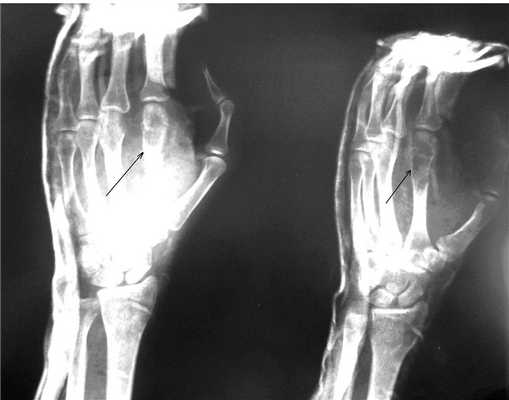

Пациентка Я., 34 года, заметила увеличение области V пястно-фалангового сустава левой кисти, через полгода начали беспокоить боли в данной области. Обратилась в СОКОД, после дообследования была госпитализирована в отделение общей онкологии с диагнозом: энхондрома V пястной кости левой кисти, для оперативного лечения (рис. 2а). Выполнено: экскохлеация очага, обработка образовавшейся костной полости при помощи аргоно-плазменной установки мощностью 60Вт. Аутопластика участком крыла левой подвздошной кости. Остеосинтез пластиной с винтами (рис. 2б). Иммобилизация гипсовой лангетой 6 недель. Пациентка наблюдается в условиях СОКОД в течение года.

| Рис.2. а) Рентгенограмма левой кисти в прямой проекции больной Я. до оперативного лечения (стрелками указана энхондрома V пястной кости). | Рис. 2 б) Рентгенограмма левой кисти в прямой проекции больной Я. после оперативного лечения спустя 3 дня (стрелкой указана зона выполненной операции с наличием металлофиксатора). |